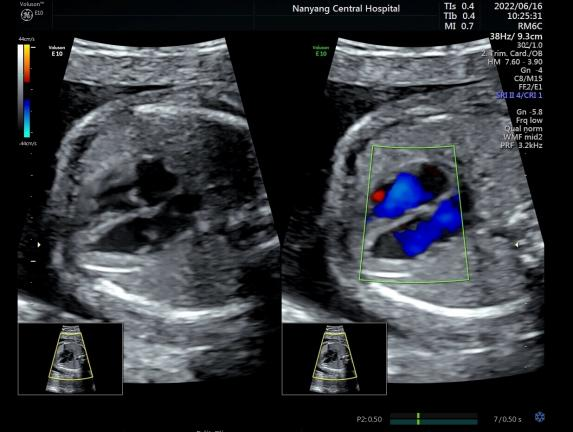

彩超是彩色多普勒超声的简称,是在B型超声的基础上,增加了彩色多普勒技术,用红色、蓝色及其亮度来显示人体组织的血流方向及速度,进一步显示目标部位的血流供应情况。当彩色多普勒功能开启的时候,图像上会出现星星点点的红色或蓝色的血流信息,称之为“彩超”。但彩色多普勒功能并不是时刻都启动的,黑白的二维图像是基础,只有基础图像清晰,才会在有需要的情况下开启“彩超”,可以更好地进一步观察目标结构,所以,“彩超”大部分时间是黑白的。

左图“黑白”,右图“彩色”